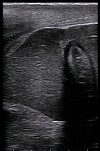

Se trata de la estandarización de la técnica ecográfica para el diagnóstico de BKD. Cabe destacar que los expertos de la compañía ya habían estandarizado el año pasado la técnica para la detección temprana de nefrocalcinosis.

Para el caso del BKD, realizaron una serie de seguimientos y categorizaciones de peces enfermos por ecografía, dependiendo del nivel de daño observado en los órganos, los que luego fueron confirmados mediante necropsia e histopatología y correlacionados en un alto nivel con el diagnóstico.

Así, para monitoreos de alerta temprana, se puede caracterizar rápidamente la condición interna de los peces con un foco en los signos de BKD, con muestreos de entre 250-300 ejemplares a un ritmo de 1-2 segundos por pez

“Ya hemos hecho categorizaciones masivas de peces que mostraron anomalías asociadas a BKD y que dieron positivo a la patología. En estos casos hemos diagnosticado el nivel de severidad de los signos internos típicos de la enfermedad en poblaciones de smolts de 40 gramos, con más de 400.000 peces ecografiados. Podemos aplicar este diagnóstico en salmón Atlántico, coho y trucha arcoíris, desde los 20-30 gramos, ya sea para entregar alertas tempranas o para categorizar poblaciones que tengan un diagnóstico positivo a BKD y dirigir los tratamientos a aquellos ejemplares con signología de menor severidad”, detalla López.

De acuerdo con el jefe Área Reproductores de Econexus, a pesar del alto porcentaje de efectividad del diagnóstico ecográfico 70%, se sugiere confirmar con técnicas como inmunohistoquímica o similares. No obstante, para la categorización de la signología típica en peces ya confirmados como positivos, la efectividad se incrementa a un 95%. Aun así, considera que la ecografía es un método valioso para el monitoreo y alerta temprana ante la aparición de anomalías internas de BKD.